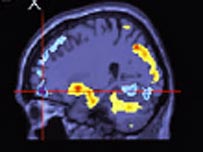

Cientistas americanos desenvolveram uma técnica de "leitura da mente", que permite que um computador identifique as imagens que uma pessoa está vendo, sugere um estudo publicado na edição desta quinta-feira da revista científica Nature. Os pesquisadores, da Universidade da Califórnia, criaram um programa que analisa imagens por ressonância magnética captadas do córtex de pessoas no momento em que estas estavam olhavam para uma série de imagens. Em testes realizados pelos cientistas, o programa foi capaz de acertar nove em cada dez imagens. Segundo os pesquisadores, a nova técnica abre caminho para o desenvolvimento de um aparelho que eventualmente seja capaz de fazer a leitura da memória ou dos sonhos ao reconstruir as imagens visuais. "Em breve talvez sejamos capazes de reconstruir a imagem de uma experiência visual apenas ao observar a atividade do cérebro. Imagine um aparelho que faz leituras do pensamento, capaz de reconstruir a imagem da experiência visual de uma pessoa em qualquer momento", afirmou Jack Gallant, que liderou o estudo. Apesar de otimistas, os cientistas afirmam que, por enquanto, a técnica pode ser aplicada apenas em imagens estáticas já que os aparelhos de ressonância magnética conseguem fazer apenas uma leitura a cada três ou quatro segundos, o que impossibilita a decodificação da atividade cerebral no caso das imagens em movimento. Decodificação Para realizar a pesquisa, os cientistas tiveram que treinar o software para decodificar a atividade cerebral de cinco voluntários ao serem estimulados visualmente com mais de mil imagens diferentes durante cinco horas consecutivas. Este treinamento ensina o software a decodificar como o cérebro de cada pessoa assimila as informações visuais, diz o estudo. No passo seguinte, os pesquisadores partiram de uma série de 120 imagens e usaram o software para prever a atividade do cérebro esperada durante a exposição dos voluntários a estas imagens. Finalmente, este segundo grupo de imagens foi exibida novamente aos voluntários enquanto eram submetidos à ressonância magnética e o programa então identificou para quais imagens os voluntários estariam olhando apenas com base nas ressonâncias, acertando 90% das vezes. Avanço Os resultados da pesquisa levantam questões sobre a privacidade das pessoas e as implicações éticas da 'leitura' dos pensamentos. De acordo com Gallant, em 30 ou 50 anos, os avanços podem ter implicações sérias na privacidade das pessoas. "Nós acreditamos que ninguém deve ser submetido a nenhuma forma de leitura mente de forma involuntária, ou sem informações suficientes ou consentimento", disse o pesquisador. Os receios com relação aos avanços na decodificação das atividades cerebrais remetem à trama do filme Minority Report – A Nova Lei, com Tom Cruise, no qual a polícia tinha capacidade de ler as mentes das pessoas e prender aquelas que tivessem pensamentos criminosos. |